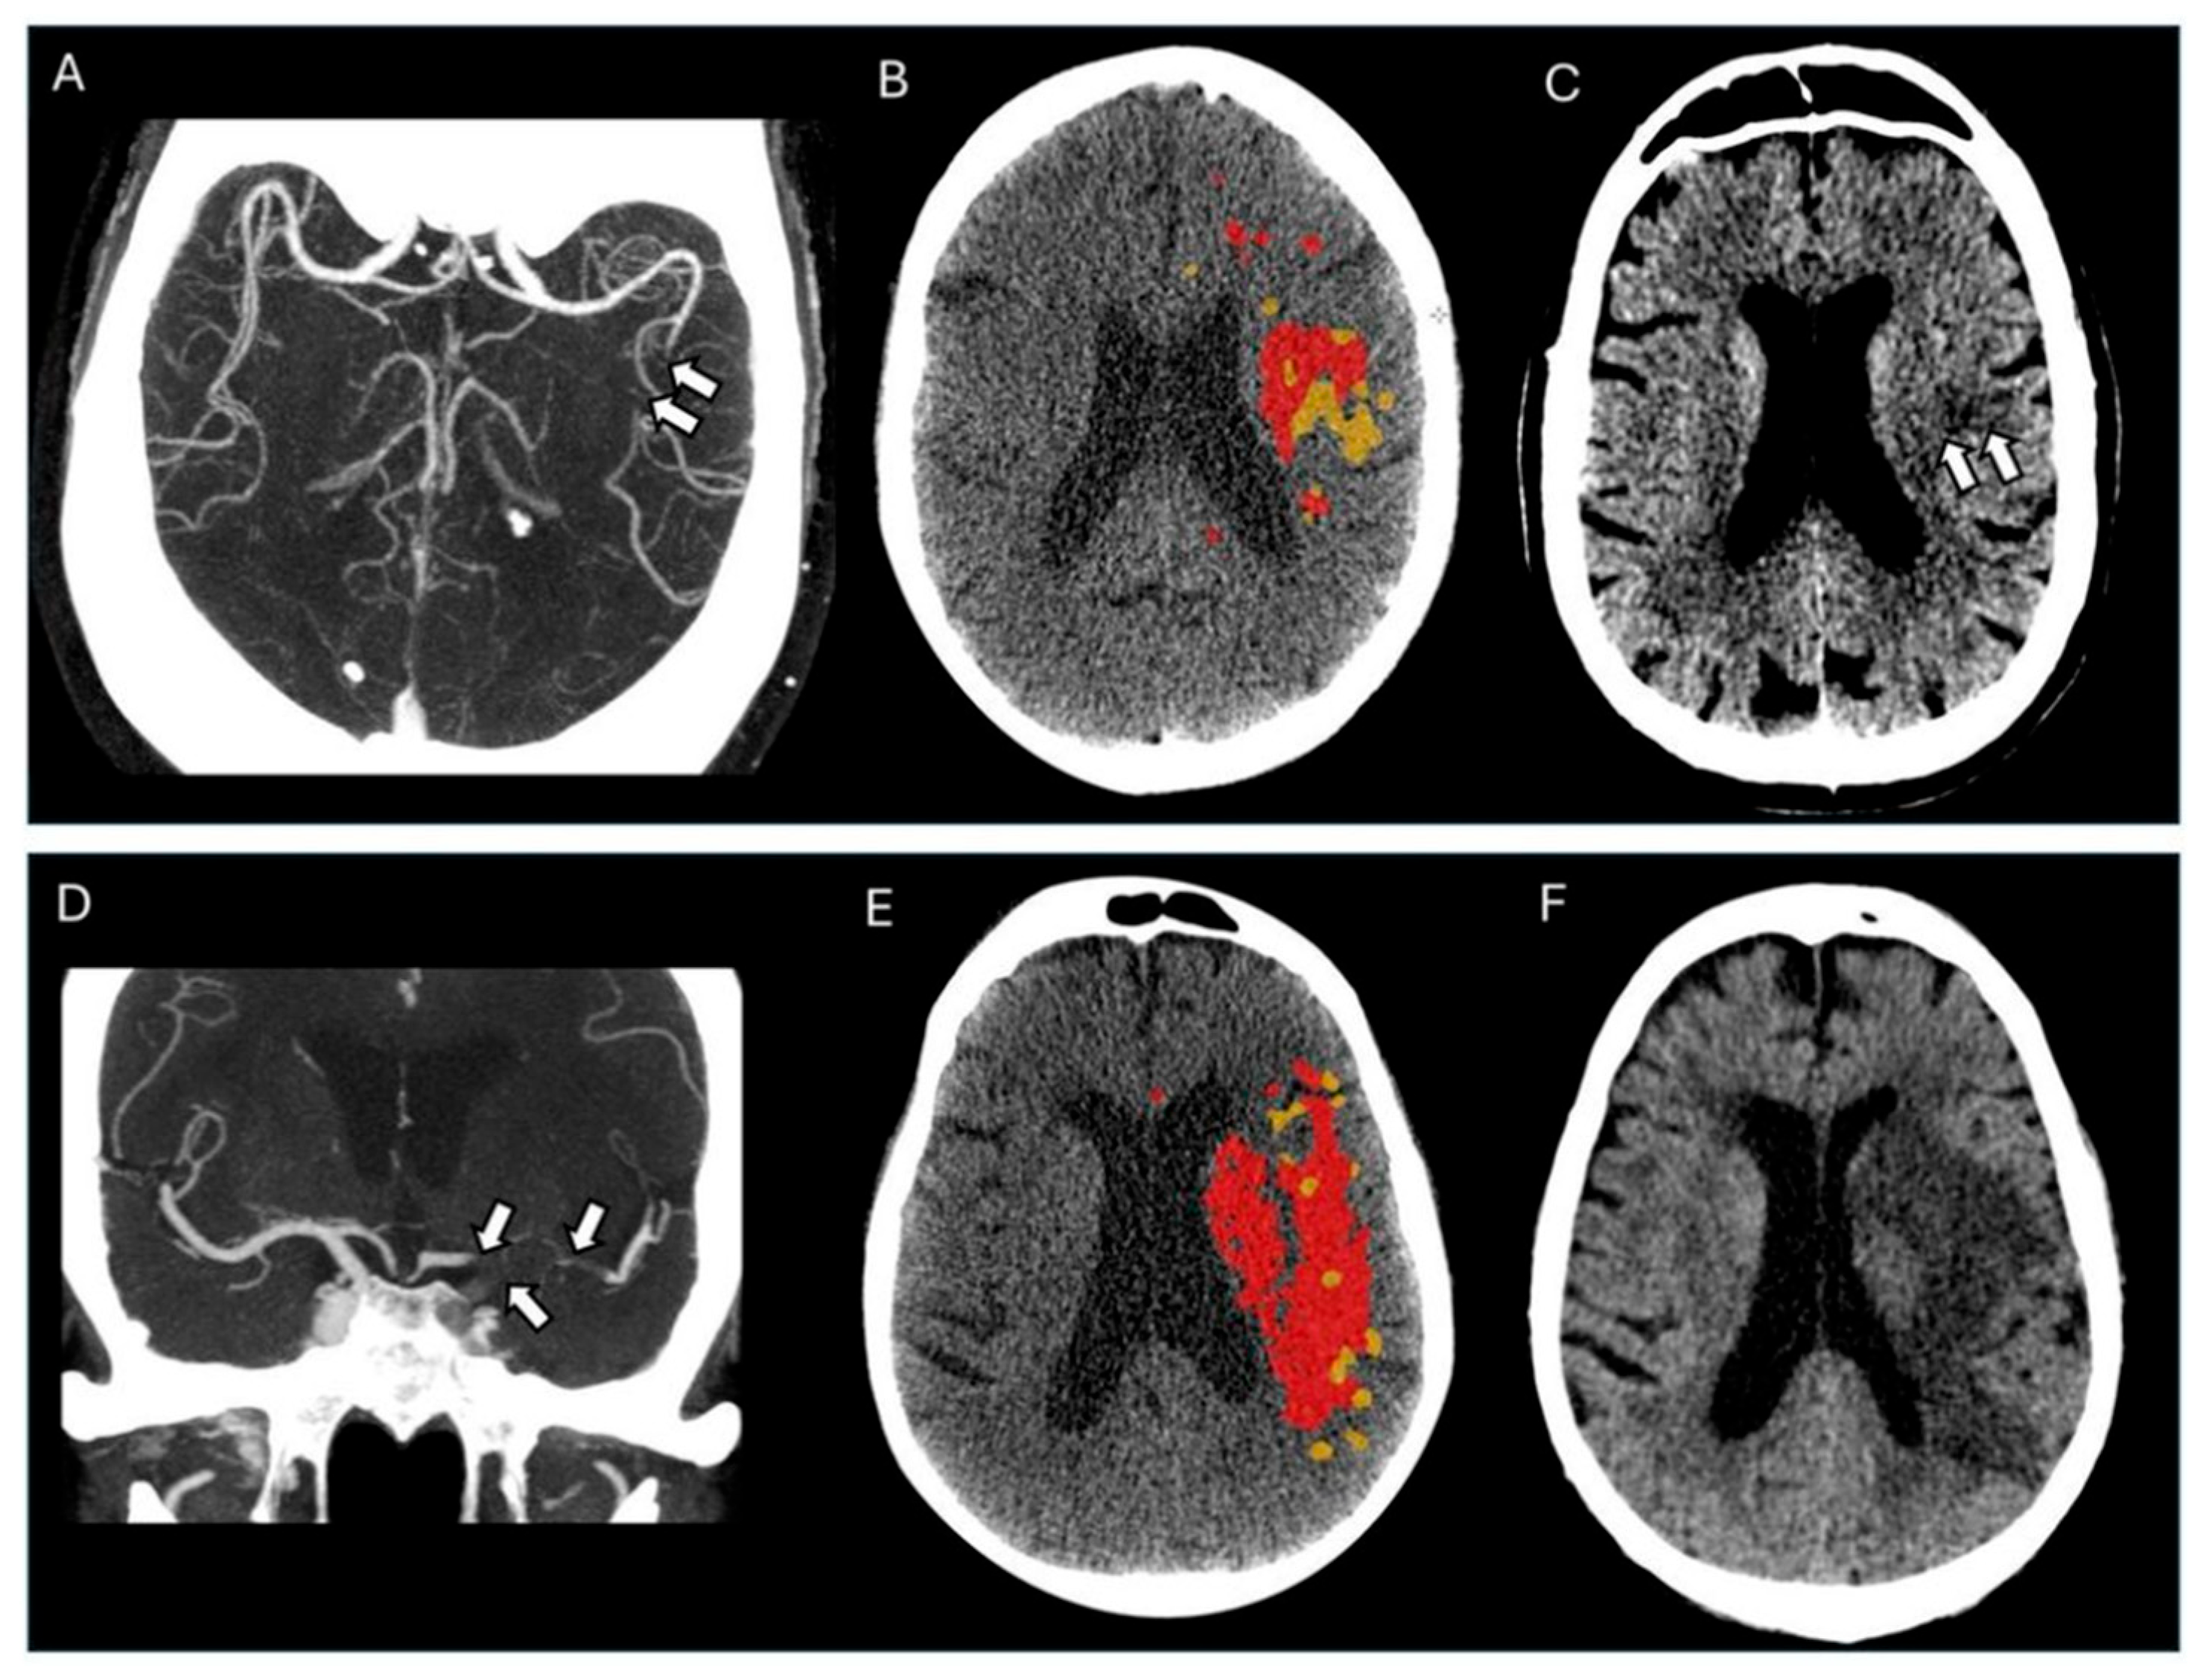

2.2. Imaging Protocol and Analyses

3. Results

3.2. Outcome Analyses